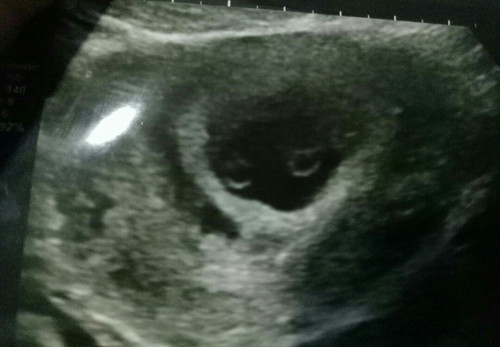

pregnat twins

Hye ada x yg preggy twins...sy smlm ada bledding tu yg pergi scan tp mcm terkejut sbb doc ckp sy preggy twin...ada x yg preggy twin share satu uri?nerves la...sbb sy baru 6 weeks 6day....*xde history family twins*